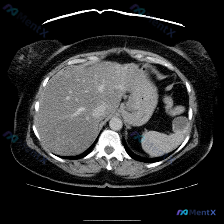

最近看到一个读片资料,预设问题是“图像中是否存在脾脏病变”,先和大家理一下完整的思路。 --- 先列一下拿到的「影像客观事实」 这是一幅上腹部CT软组织窗横断面图像: 1. 肝脏:轮廓平整,实质密度均匀,肝内血管走行清晰,无受压移位; 2. 脾脏:划重点——形态正常、大小正常、实质密度均匀,未见局灶...

今天看到一个很有意思的影像案例,用户一开始就预设了「脾脏病变」的存在,但当我仔细看完这张单层面的上腹部CT平扫后,发现结论可能和预设不太一样。整理一下思路和大家分享。 --- 先看影像基础信息 这是一张上腹部CT横断面软组织窗图像,层面清晰,软组织对比度良好,没有明显运动或金属伪影。能看到肝脏、胃、...